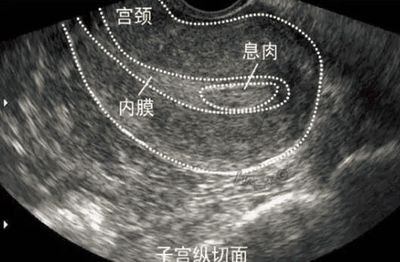

- 內(nèi)膜準(zhǔn)備:通過(guò)B超監(jiān)測(cè)子宮內(nèi)膜厚度與形態(tài),確保其達(dá)到適合胚胎著床的標(biāo)準(zhǔn)(通常建議厚度在8-12mm,三線征明顯)。